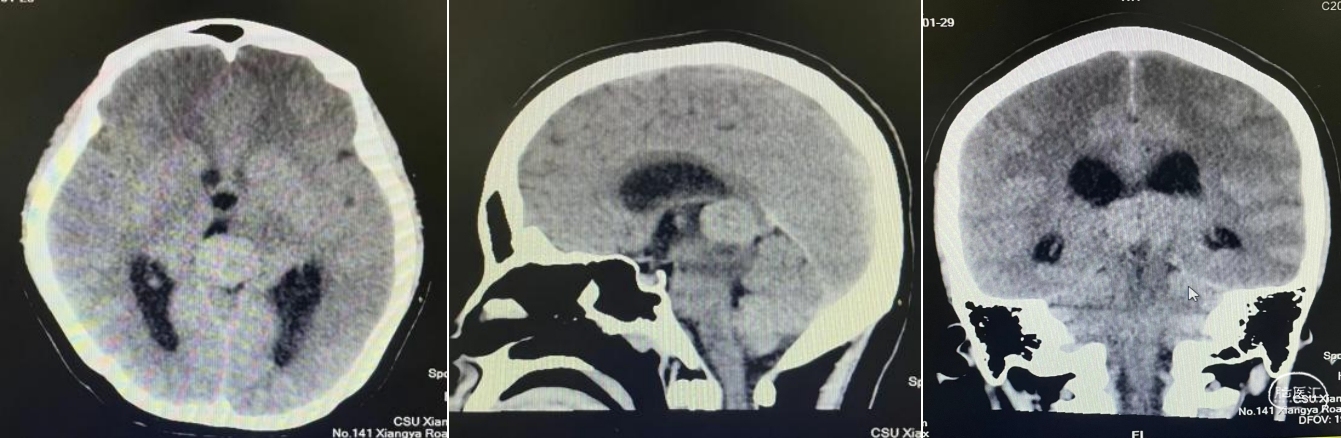

头部CT平扫:松果体区可见软组织肿块灶,大小约为27mmx23mm,平扫CT值为36HU。边缘可见斑点状钙化灶,邻近脑实质可见片状水肿低密度灶,慕上脑室积水扩张,双侧侧脑室旁可见对称性低密度灶。